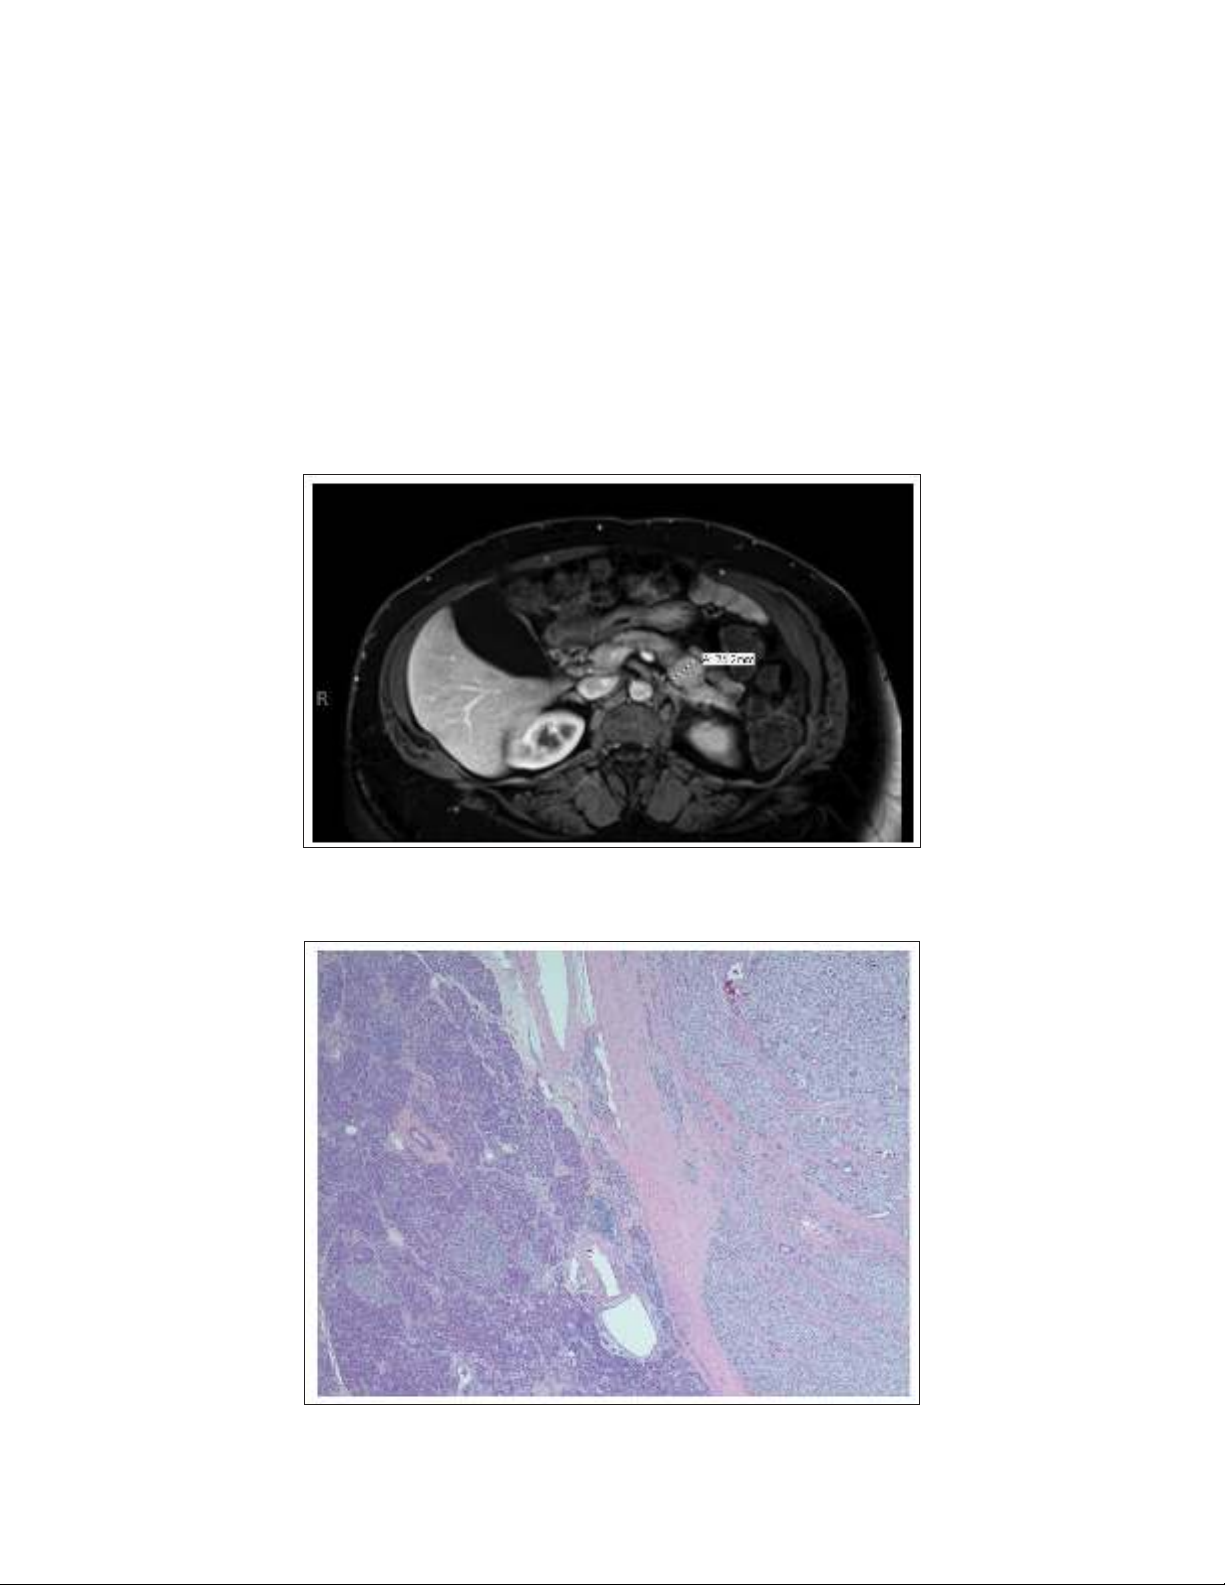

Magnetic resonance imaging (MRI) of the abdomen

(with and without contrast) was undertaken and demon-

strated a 2.4-cm, mildly hypervascular lesion in the pancre-

atic tail and a 0.9-cm, uncinate process lesion with mild

T2 hyperintensity (Fig. 1). An indium (In-111) pentet-

reotide scan performed was negative for a pentetreotide-

avid neoplasm.

Fig. 1. Magnetic resonance image of the abdomen and pelvis with and without contrast. There is

a 2.4-cm, mildly hypervascular lesion in the pancreatic tail.

Fig. 2. Insulinoma with adjacent normal pancreas. This figure shows a well-circumscribed and

encapsulated lesion comprised of monotonous-appearing cells on hematoxylin and eosin stain

(×2).